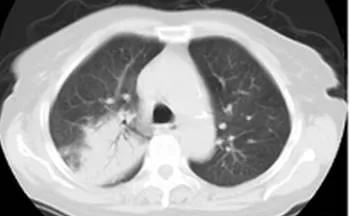

肺炎支原体肺炎的主要临床表现是反复发热、咳嗽,肺部体征与临床表现及影像学不一致,影像学表现肺间质浸润影、大叶性肺实变和肺门淋巴结肿大。部分患儿有多系统受累,如麻疹样或猩红热皮疹、心肌炎、溶血性贫血、心肌炎或心包炎、格林巴利综合征等。

肺炎支原体肺炎首选大环内酯类抗生素,临床上以阿奇霉素为首选药物,此外红霉素也可使用,8岁以上儿童可选用盐酸米诺环素或多西环素,同时应用吸入性糖皮质激素等雾化吸入,对于难治性MPP使用肾上腺糖皮质激素治疗。肺不张、肺实变吸收不明显者可使用电子支气管镜治疗。

选择支气管镜治疗的指征: (1) 在常规检测、治疗后,疗效不佳、病原不明,疑有特殊病原感染、混合病原感染或耐药菌感染时。(2) 可能有非感染病因并存,如气道异物、新生物、先天气道狭窄等。(3) 有明显气道阻塞征象时:影像学提示肺不张、气道阻塞所致单侧肺气肿、纵隔气肿、单侧或双侧肺实变,尤其时实变内支气管充气征消失、树芽征等小气道病变等。(4) 肺炎支原体、腺病毒、流感病毒等感染或某些重症细菌性肺炎有阻塞征象时。(5) 使用抗感染药物治疗后症状、体征虽有好转,但2周后影像学检查提示病灶吸收<50%者。